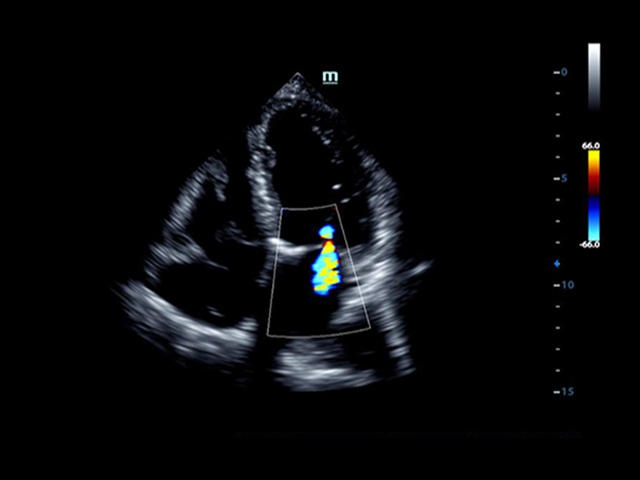

Mindray DC-8 Exp – это ультразвуковой аппарат с архитектурой mQuadro и функцией эластографии Natural Touch. Он оснащен высококлассным 21-дюймовым TFT-монитором с разрешением Full HD. Данный аппарат представляет интерес для специалистов, занимающихся обследованием мягких тканей с использованием эластографии. Режим объемного 4D-сканирования позволяет получать максимально точные диагнозы, сокращая количество неэффективных процедур.

Кардиология:

Да

• LVO - опция проведения исследования левого желудочка с применением контрастных веществ